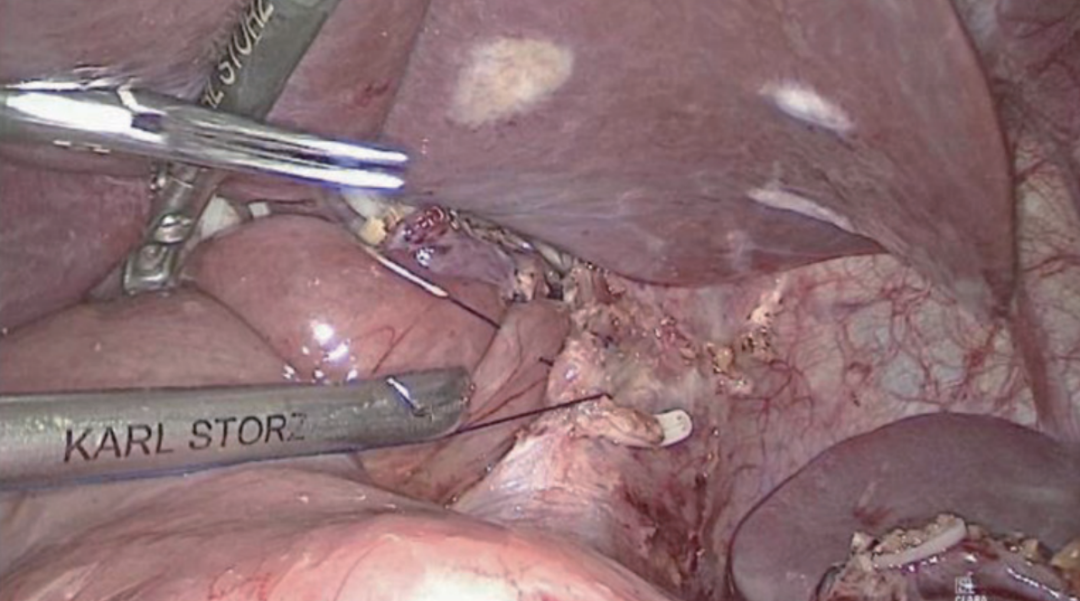

切开食管断端右侧角约5 mm,该切口应该与断端平行,即与食管纵行肌垂直,以防吻合时食管撕裂,经该口将胃管穿出(图8~图9)。用60 mm直线切割吻合器钉仓臂自远端向近端插入远端空肠盲端,抵钉臂在胃管引导下插入食管,行食管-空肠重叠顺蠕动侧侧吻合(Overlap吻合)(图10~图11)。吻合时建议将空肠盲端塞入下纵隔中,以避免膈肌卡压吻合口上端,造成吻合口并发症(图12~图13)。用倒刺线关闭共同开口(共同开口关闭方向应与肠管长轴方向垂直),先全层连续缝合,后浆肌层连续缝合包埋(图14~图15)。将吻合处空肠缝合固定于左侧膈肌脚,防止空肠盲端滑出下纵隔;并固定Y袢于肝胃韧带、十二指肠,防止术后空肠活动度过大导致扭转(图16~图19)。完成食管-空肠重叠顺蠕动侧侧吻合(Overlap吻合)。

图10 在胃管引导下插入吻合器抵钉臂(一)

图11 在胃管引导下插入吻合器抵钉臂(二)